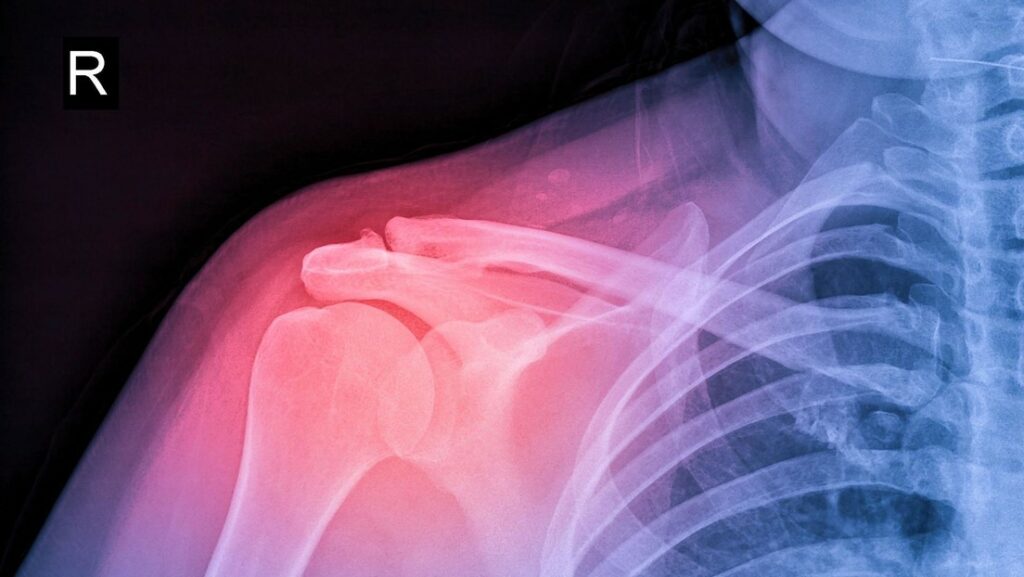

El estudio fue realizado con ratas “debido a la similitud de su estructura corporal con el cuerpo humano”, declaró Samaneh Arab, investigadora en el tratamiento de lesiones óseas mediante células madre y esqueletos óseos de la misma universidad. Arab contó que “para la investigación, se creó una lesión ósea en un ratón y luego se reconstruyó utilizando una impresora 3D“.

El trasplante tuvo éxito y una de las ratas necesitó ocho semanas para regenerar el hueso, mientras otras necesitaron alrededor de 12 semanas. Además, la investigadora afirmó que las pruebas demostraron que el nivel de toxicidad del procedimiento médico realizado es bajo.